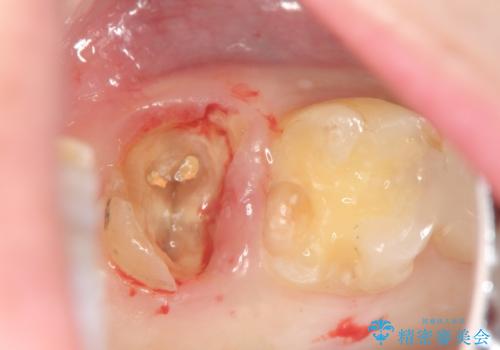

歯髄方向 歯肉方向へと深い 2種類の大きな虫歯

#17は失活歯で歯肉方向への縁下カリエス、#16は生活歯であるものの歯髄ギリギリの処置となるであろうとが予想される治療です。

歯周外科、マイクロスコープを用いた虫歯治療を行い歯を残す治療計画を立てます。

深い虫歯には歯周外科、マイクロスコープを用いた丁寧な虫歯の除去を行うことで歯の神経や歯そのものを残すことが可能になります。